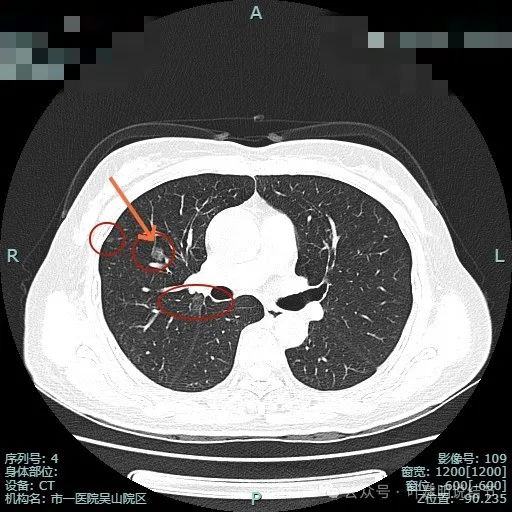

右上主病灶出现(病灶2),离肺门部非常近,密度较淡。

病灶1有明显叶间裂牵拉影响;病灶2密度虽淡,但轮廓清,贴着支气管壁。也有小血管走向病灶。

病灶1密度已经淡了;病灶2刚好位于上叶支气管发现后段支气管处,与支气管壁没显著间隙。